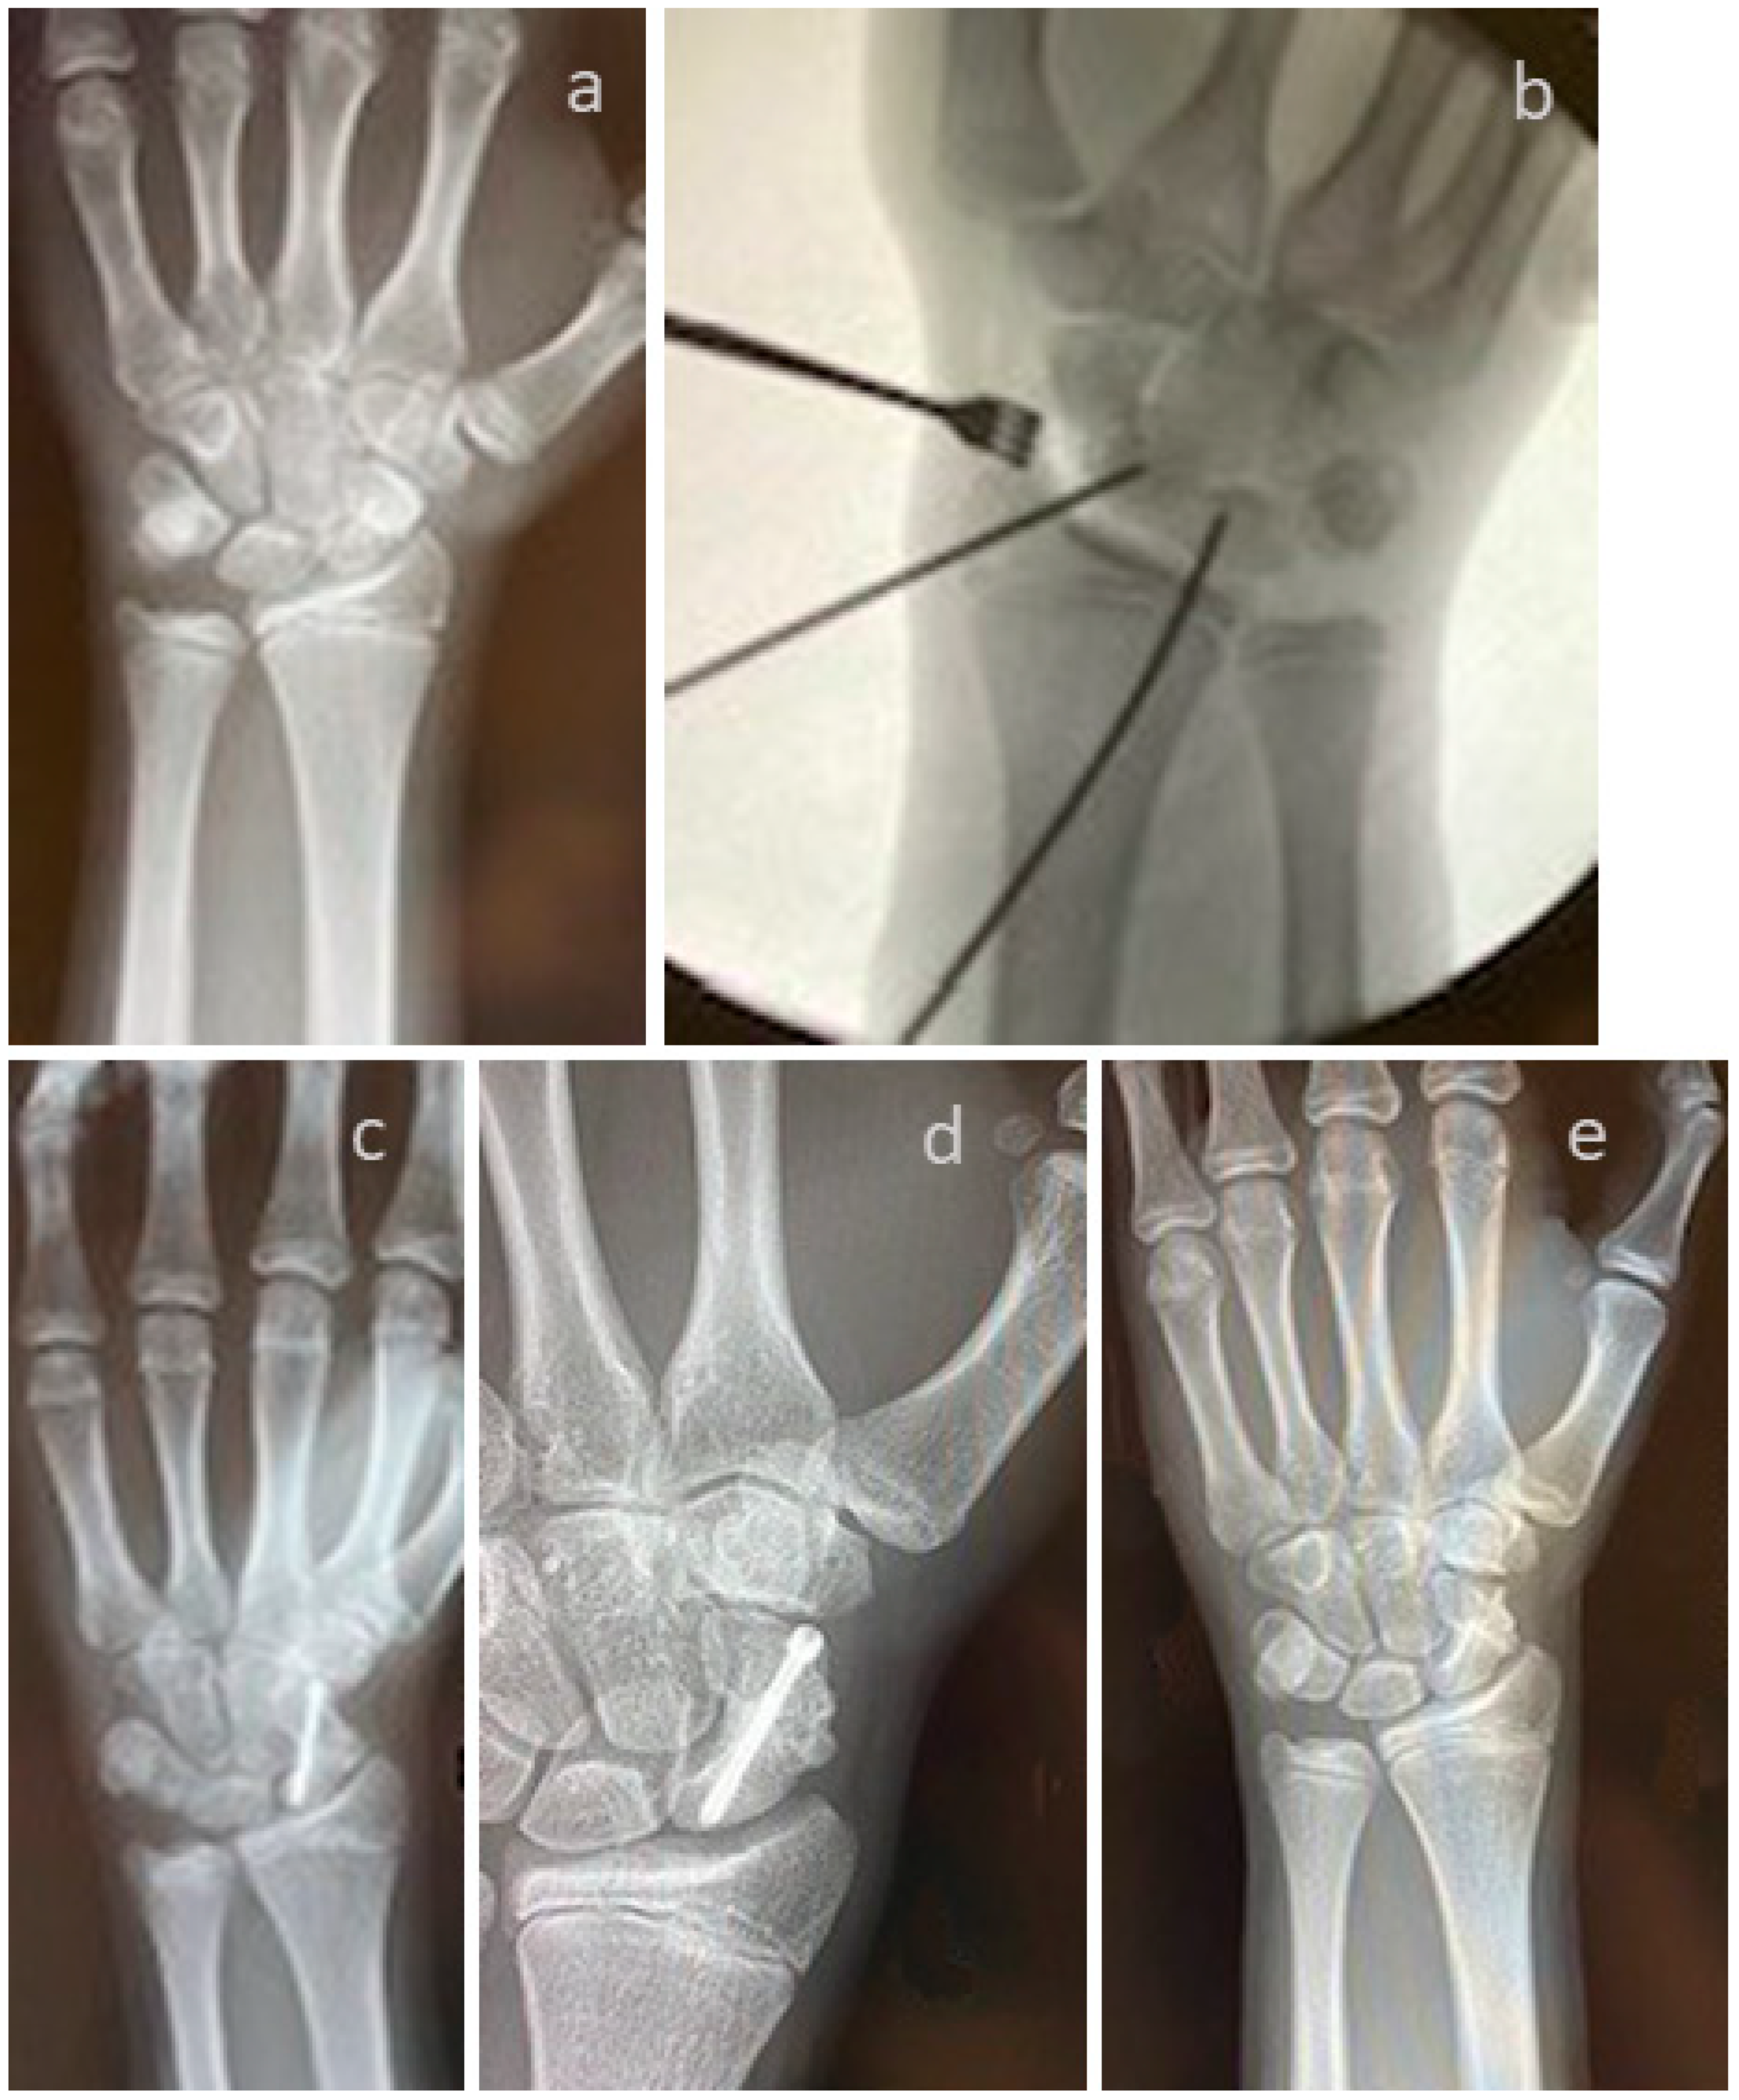

3.4. Selected Case Descriptions